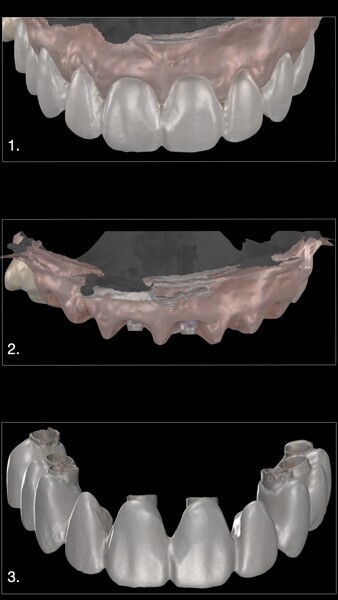

4. Digital impression of the temporary restoration: We also took a digital impression of the temporary restoration outside the mouth. This would be used by the dental technician to create a working model by copying the custom emergence profiles from the design and making necessary modifications for the definitive restoration (Figs. 30 & 31).

The final step for the patient is the delivery of the definitive restoration. In this FP-1 case with eight implants fully integrated and high papillae, we opted for a design that would separate the restoration into four three-unit bridges (Fig. 32). This approach provides several advantages:

1. Reduced restoration span: By dividing the restoration into smaller bridges, we reduce the span of each restoration, which helps lower the overall tension on the restoration. This eliminates the need for a titanium bar, which would typically be required for an FP-3 design.

2. Improved implant angulation: The separation of the restoration allows for better angulation between the implants placed on the left and right sides of the arch. This not only improves the overall function but also reduces the risk of fracture of the zirconia restoration, ensuring greater longevity.

3. Soft-tissue aesthetics and passive fit: The most important aspect in this case was the appearance of the soft tissue. Upon insertion of the definitive restoration, we achieved a perfect result and no blanching of the gingivae, indicating proper tissue support. Furthermore, there was no tension upon insertion, ensuring a comfortable fit and long-term stability of the zirconia restorations (Figs. 33–35).